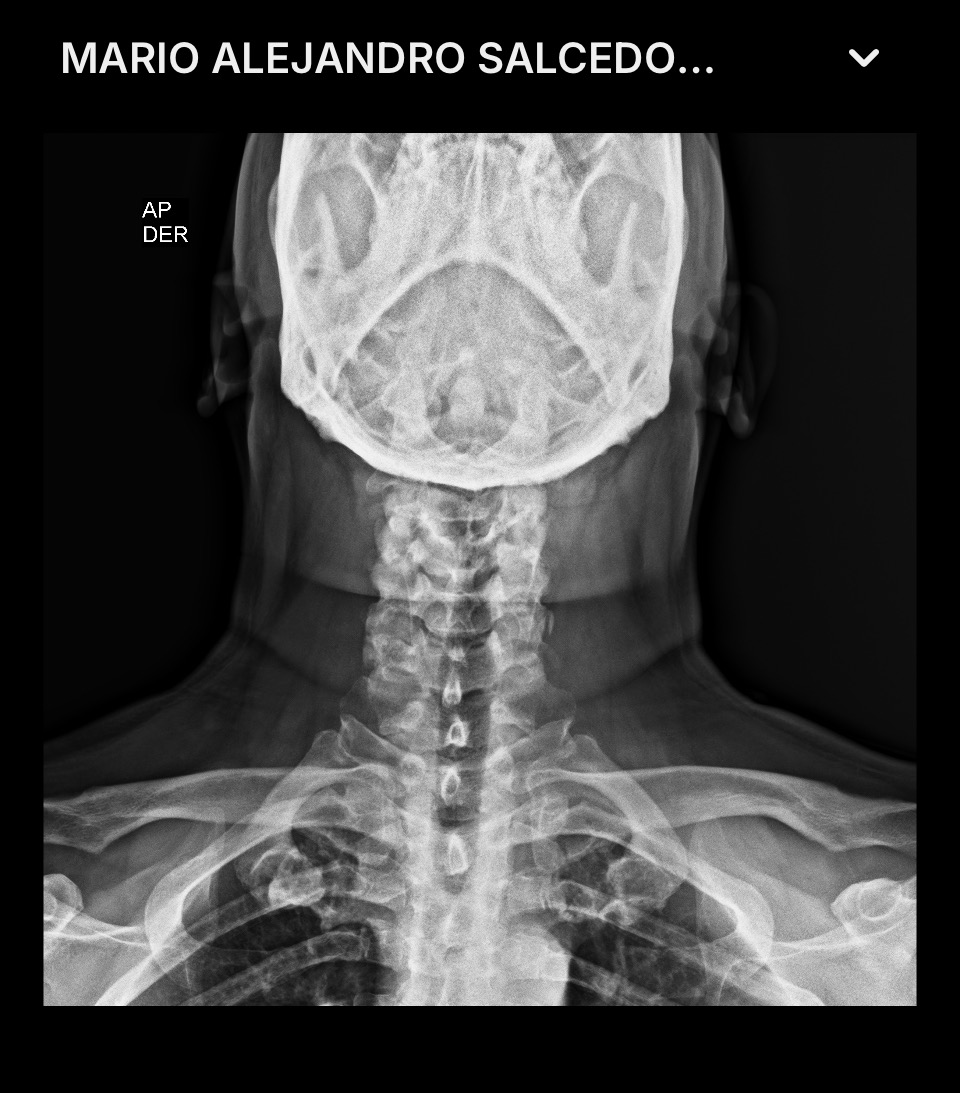

El día martes, 4 de noviembre de 2025, fuimos a ver a un nuevo doctor neurocirujano, que me envió de carácter urgente a realizarme nuevos estudios (RX's y resonancias magnéticas), así como también análisis de sangre y orina.

Este doctor neurocirujano me comentó que ya estaba en una situación de carácter urgente y que tenía que ser intervenido quirúrgicamente, ya que mi médula espinal está comprometida, diciéndome, en otras palabras, que en cualquier momento puedo quedar sentado. Pero que si me opero en este momento, tendría una esperanza para poder recuperarme y disfrutar de una vida normal acompañado de mi esposa e hijas.